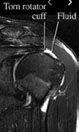

DIAGNOSING ROTATOR CUFF TEARS

Diagnosis of a rotator cuff tear requires the combination of a thorough physical examination, detailed history and review of any imaging that you’ve had. Other conditions can masquerade as a rotator cuff tear and a diagnosis cannot be made without these three aspects of your presentation. The shoulder requires a thorough physical examination by an experienced therapist, once the diagnosis is complete, a treatment plan is prepared to get you back to the things you love.